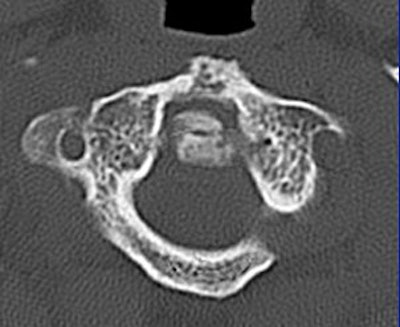

![]() |

| Image G |

The 0.5-mm slices offer fine bone detail, but pay a price on the soft-tissue images in terms of soft-tissue differentiation. Whereas the thicker (5-mm) slices fail to show the bone detail of the fracture well, but possess greater contrast resolution on the soft-tissue window to differentiate spinal cord from surrounding spinal fluid.